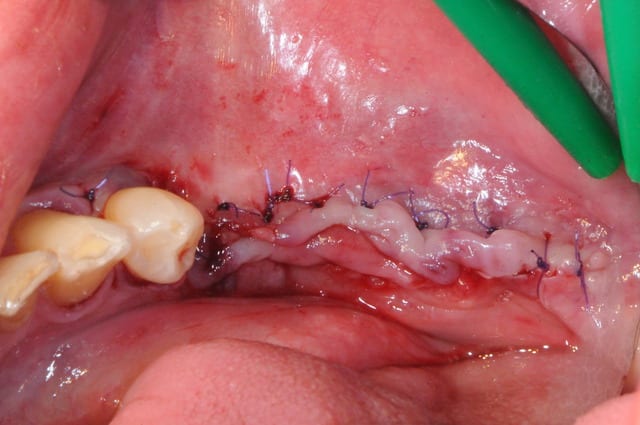

1-2

enfin, mise en place d'une membrane péricarde Jason de 30*50 (je crois)

3- j'ai profité de la stabilité de la mesh comme piquet de tente pour bourrer la cavité avec du MAXGRAFT (os humain)..

4-5- un peu de A-PRF (the king !)

6- le plus important des sutures hermétiques et une gencive immobile en fin d'intervention

7 les radios post-op